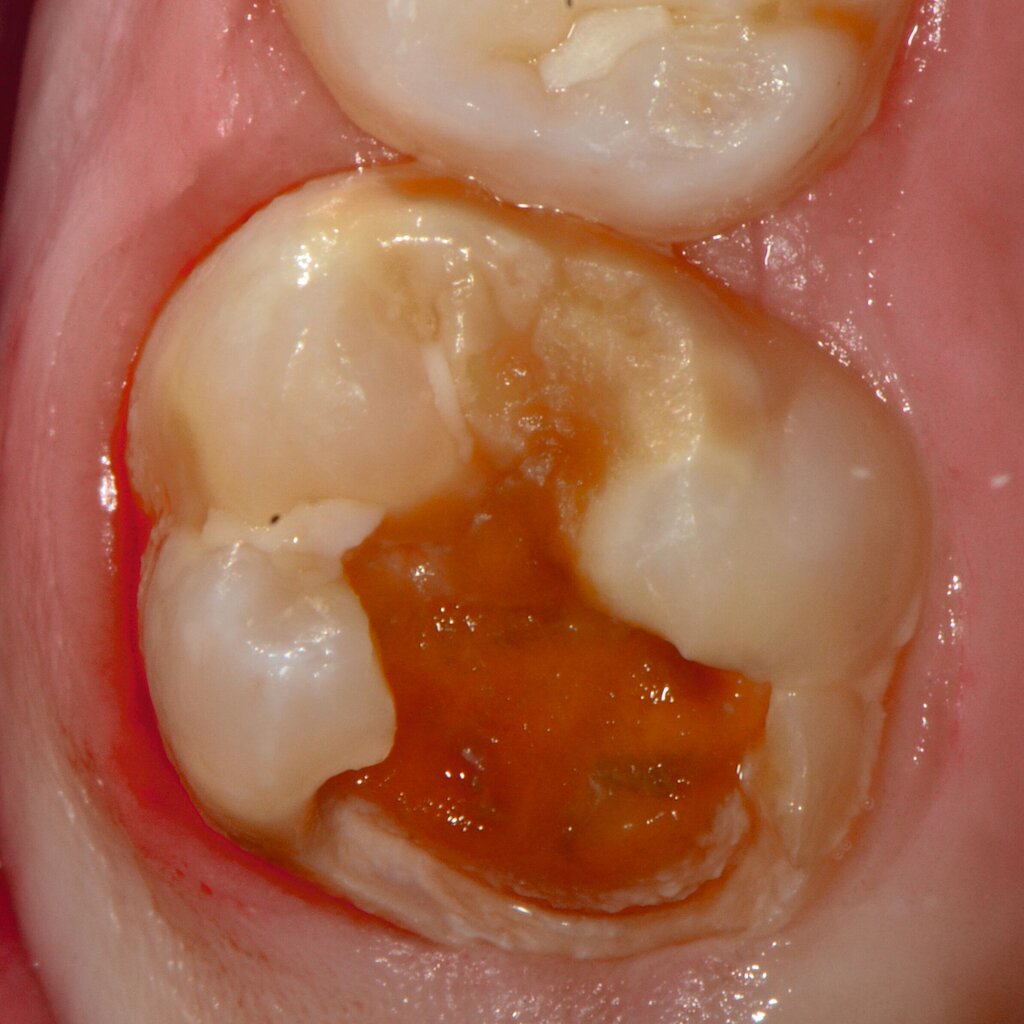

An umfangreich hypomineralisierten Zähnen können Schmelzeinbrüche (engl.: „enamel breakdown“ oder „enamel desintegration“, Abbildung 5) auftreten [Lygidakis et al., 2010; 2022]. Da diese oftmals die Folge einer fehlenden Belastungsfähigkeit des Zahnschmelzes sind und erst nach der Einstellung der Zähne in die Okklusion auftreten, werden sie auch als posteruptive Schmelzeinbrüche bezeichnet. Sie sind häufig im Bereich der Kauflächen beziehungsweise Höcker der Molaren zu finden, führen zur Dentinexposition und damit einhergehend zu ausgeprägten Hypersensitiven insbesondere bei Kindern, deren Zähne gerade erst durchgebrochen sind [Linner et al., 2021].

Frontzähne sind seltener von MIH-bedingten Schmelzeinbrüchen und Hypersensitivitäten betroffen. Von den posteruptiven Oberflächeneinbrüchen sind präeruptive Defekte abzugrenzen. Diese Zähne brechen bereits mit einem vorhandenen Oberflächendefekt in die Mundhöhle durch.

Für die Dokumentation und Klassifikation der MIH wurden verschiedene Systeme vorgeschlagen. Als historisch und veraltet gilt der (modifizierte) DDE-Index. Demgegenüber haben die Kriterien der EAPD – abgegrenzte Opazitäten (Abbildung 3 und 4), Schmelzeinbrüche (Abbildung 5), atypische Restaurationen (Abbildung 6) – mittlerweile die weiteste Verbreitung gefunden. Diese wurden 2003 erstmals zur Beschreibung der MIH auf empirischer Basis publiziert [Weerheijm et al., 2003] und den Jahren 2010 und 2022 im Rahmen der damaligen MIH-Workshops bestätigt [Lygidakis et al., 2010; 2022].